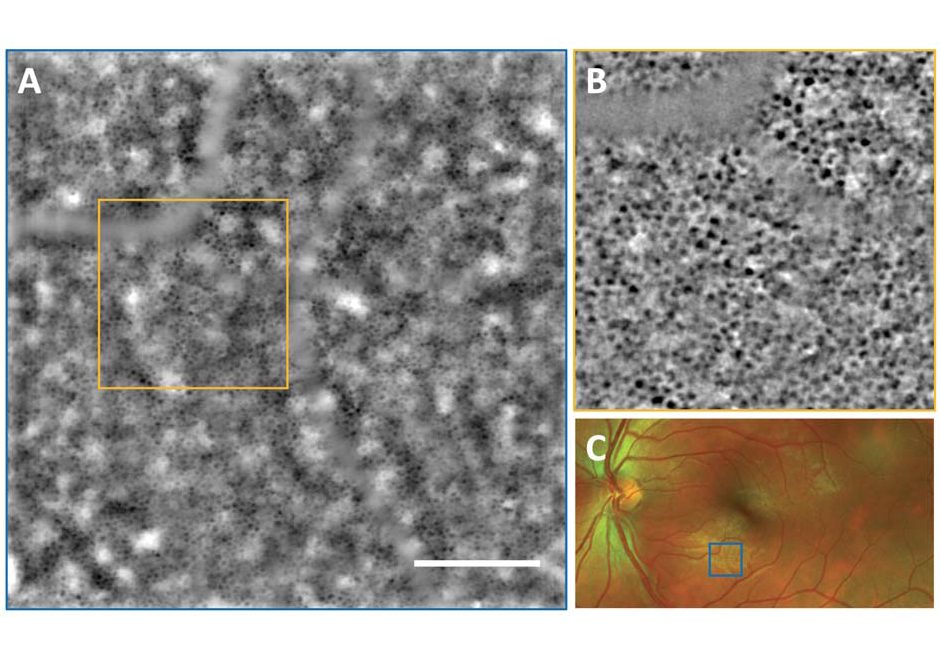

Kowalczuk L., Dornier R., Navarro A., Jeunet F., Moser C., Behar-Cohen F., Mantel I., Adaptive Optics-Transscleral Flood Illumination Imaging of Retinal Pigment Epithelium in Dry Age-Related Macular Degeneration, Cells (2025), 14(9), 633. doi: 10.3390/cells14090633. |

Govindahari V., Dornier R., Ferdowsi S., Moser C., Mantel I., Behar-Cohen F., Kowalczuk L., High-Resolution Adaptive Optics-Trans-scleral Flood Illumination (AO-TFI) Imaging of Retinal Pigment Epithelium (RPE) in Central Serous Chorioretinopathy (CSCR), Scientific Reports, 14.1 (2024):13689. doi: 10.1038/s41598-024-64524-4. |

Kowalczuk L., Dornier R., Kunzi M., Iskandar A., Misutkova Z., Gryczka A., Navarro A., Jeunet F., Mantel I., Behar-Cohen F., Laforest T., Moser C., in vivo Retinal Pigment Epithelium Imaging using Transscleral OPtical Imaging in healthy eyes, Ophthalmology Science, 100234 (2022). |

dos Santos F., Laforest T., Künzi M., Kowalczuk L., Behar-Cohen F., and Moser C., Fully automated detection, segmentation, and analysis of in vivo RPE single cells, Eye, June 2020. |

Laforest T., Künzi M., Kowalczuk L., Carpentras D., Behar-Cohen F. and Moser C. , Transscleral optical phase imaging of the human retina, Nature Photonics, March 2020. |